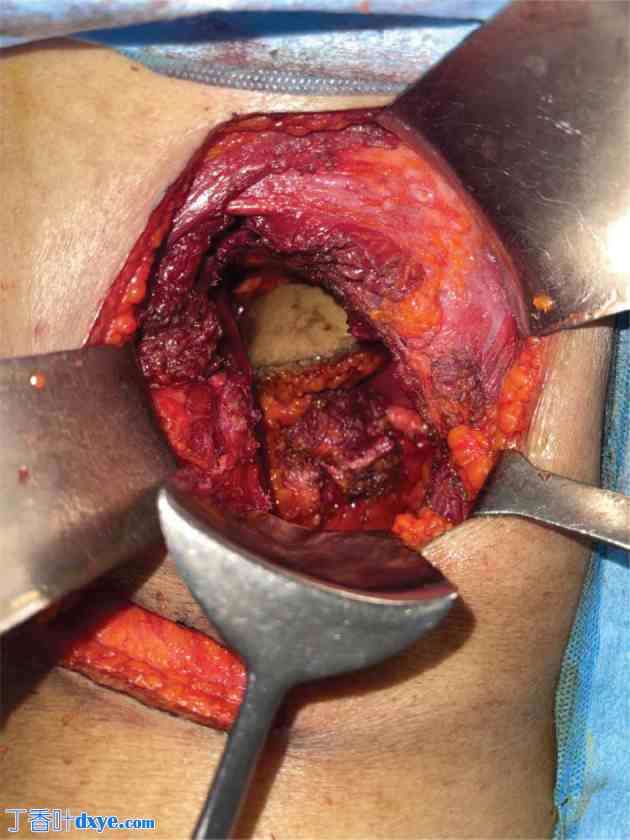

患者取半俯卧位,标记 PCNL 瘢痕(图 5),并沿边缘切开。通过切除下方的浅层和深层腹肌,将切口加深至腹膜腔。识别并切除两条含有肿瘤的 PCNL 通道(图 6 和图 7)。

切除包含皮肤及斜行经皮肾镜取石术(PCNL)皮下组织的标本,并用足够的软组织覆盖周围组织,将其推入腹腔,以防止组织溢出(图8)。